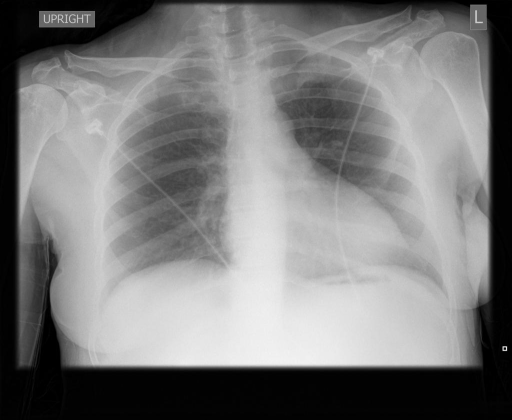

In this work, we developed computer-aided diagnosis system that can automatically detect thoracic diseases present in Chest X-rays. Specifically, we developed a multi-head self-attention convolutional network based multi-label classification framework for predicting the presence of common thoracic diseases on four of the largest publicly available chest X-ray datasets, namely, ChestX-ray14, CheXpert, MIMIC-CXR-JPG, and IU-CXR. Fig. 2 shows sample chest X-ray from four datasets having positive cardiomegaly. The block diagram of our proposed model for the identification 111We will use the term identification and classification interchangeably. of common thoracic diseases is shown in Fig. 1.

(a) ChestX-ray14

(b) CheXpert

(c) MIMIC-CXR-JPG

(d) IU-CXR

Figure 2: Randomly sampled chest X-ray having Cardiomegaly from each of the four datasets: ChestX-ray14, CheXpert, MIMIC-CXR-JPG, and IU-CXR.